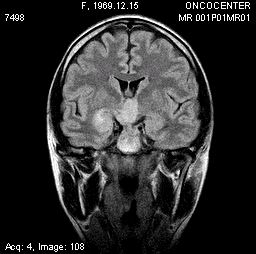

Описываем клинический случай стереотаксической брахитерапии, выполненной в Уральском межтерриториальном нейрохирургическом центре (ГБУЗ СО Свердловский областной онкологический диспансер), пациентке К. 31 год с глиальной опухолью диэнцефальной области (дна III желудочка). Данные МРТ головного мозга представлены на слайдах.

Этапы стереотаксической брахитерапии представлены на слайдах ниже.